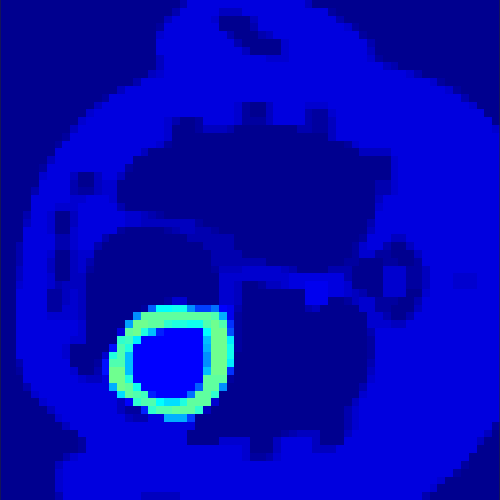

5.2 Monte Carlo Simulation

In order to test the behaviour of the proposed method in a more realistic, random-based test case, we performed a Monte Carlo simulation for dynamic SPECT imaging. First, we created a simple image phantom consisting of an outer and two inner circles which represents the structure of the region of interest (see figure 8(a)). Within those regions we assumed concentration curves over a time period of 90 time steps as displayed in figure 8(b). Based on the tracer intensity in an image frame at each time step, we created a variable number of random decay events (where the number is proportional to the average concentration in one pixel in the whole image frame per time step) with a probability proportional to the concentration in every subregion. They are detected by a virtual double head gamma camera rotating around the patient by 46 degrees per time step, which consists of 374 detector bins. Every simulated decay event is projected onto the scanner and counted by the corresponding detector bin.

In two different tests we fixed the number of events counted by the detector equal to (resp. ) times the average concentration in one pixel. The resulting sinogram images of the accumulated counts in each bin are shown in figure 9.

Based on the sinogram data we applied the proposed algorithm in order to reconstruct the original image sequence. The results for both test cases are shown in figure 10.

As one can see, the method is able to reconstruct the regions properly, even in case of a low count number. Within a number of iterations (average of 100 outer and 10000 inner iterations), the algorithm presents a reasonable reconstruction of the region of interest and the corresponding regional tracer concentration curves. Here, the parameters were not optimized as in the case of the synthesized data sets in the previous section, but kept fixed as , and . With futher optimized parameter values one could possibly provide even better results.